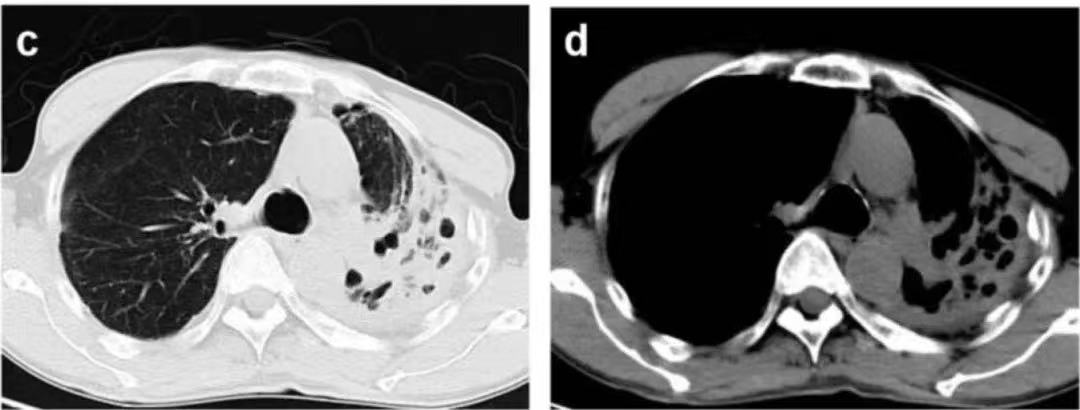

胸部CT顯示左肺上葉有慢性感染和受損病灶

“肺部CT看起來不像是肺結核。我們反復留了很多次痰涂片都沒有找到結核桿菌,如果是結核分枝桿菌或肺曲霉菌,不該如此反反復復、控制不住!”周華主任表示。根據豐富的臨床經驗,他抽取了支氣管肺泡灌洗液(BALF)送往臨床微生物室培養。